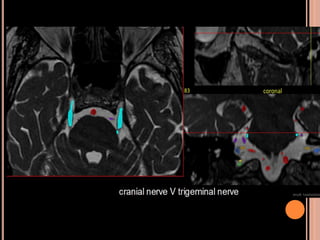

 Schwannomas vestibulares:

o 5° par (trigêmio): 2° sítio mais acometido;

SCWHANNOMAS

Pequenas lesões no CAI, bem mais caracterizada

nas aquisições volumétricas(3D CISS);

Aspecto de “sorvete de casquinha” quando lesões

maiores com extensão pontocerebelar;

Hipo em T1 e hiper heterogêneo em T2;

Impregnação pelo Gd homogênea se pequenos e

heterogênea se grandes;